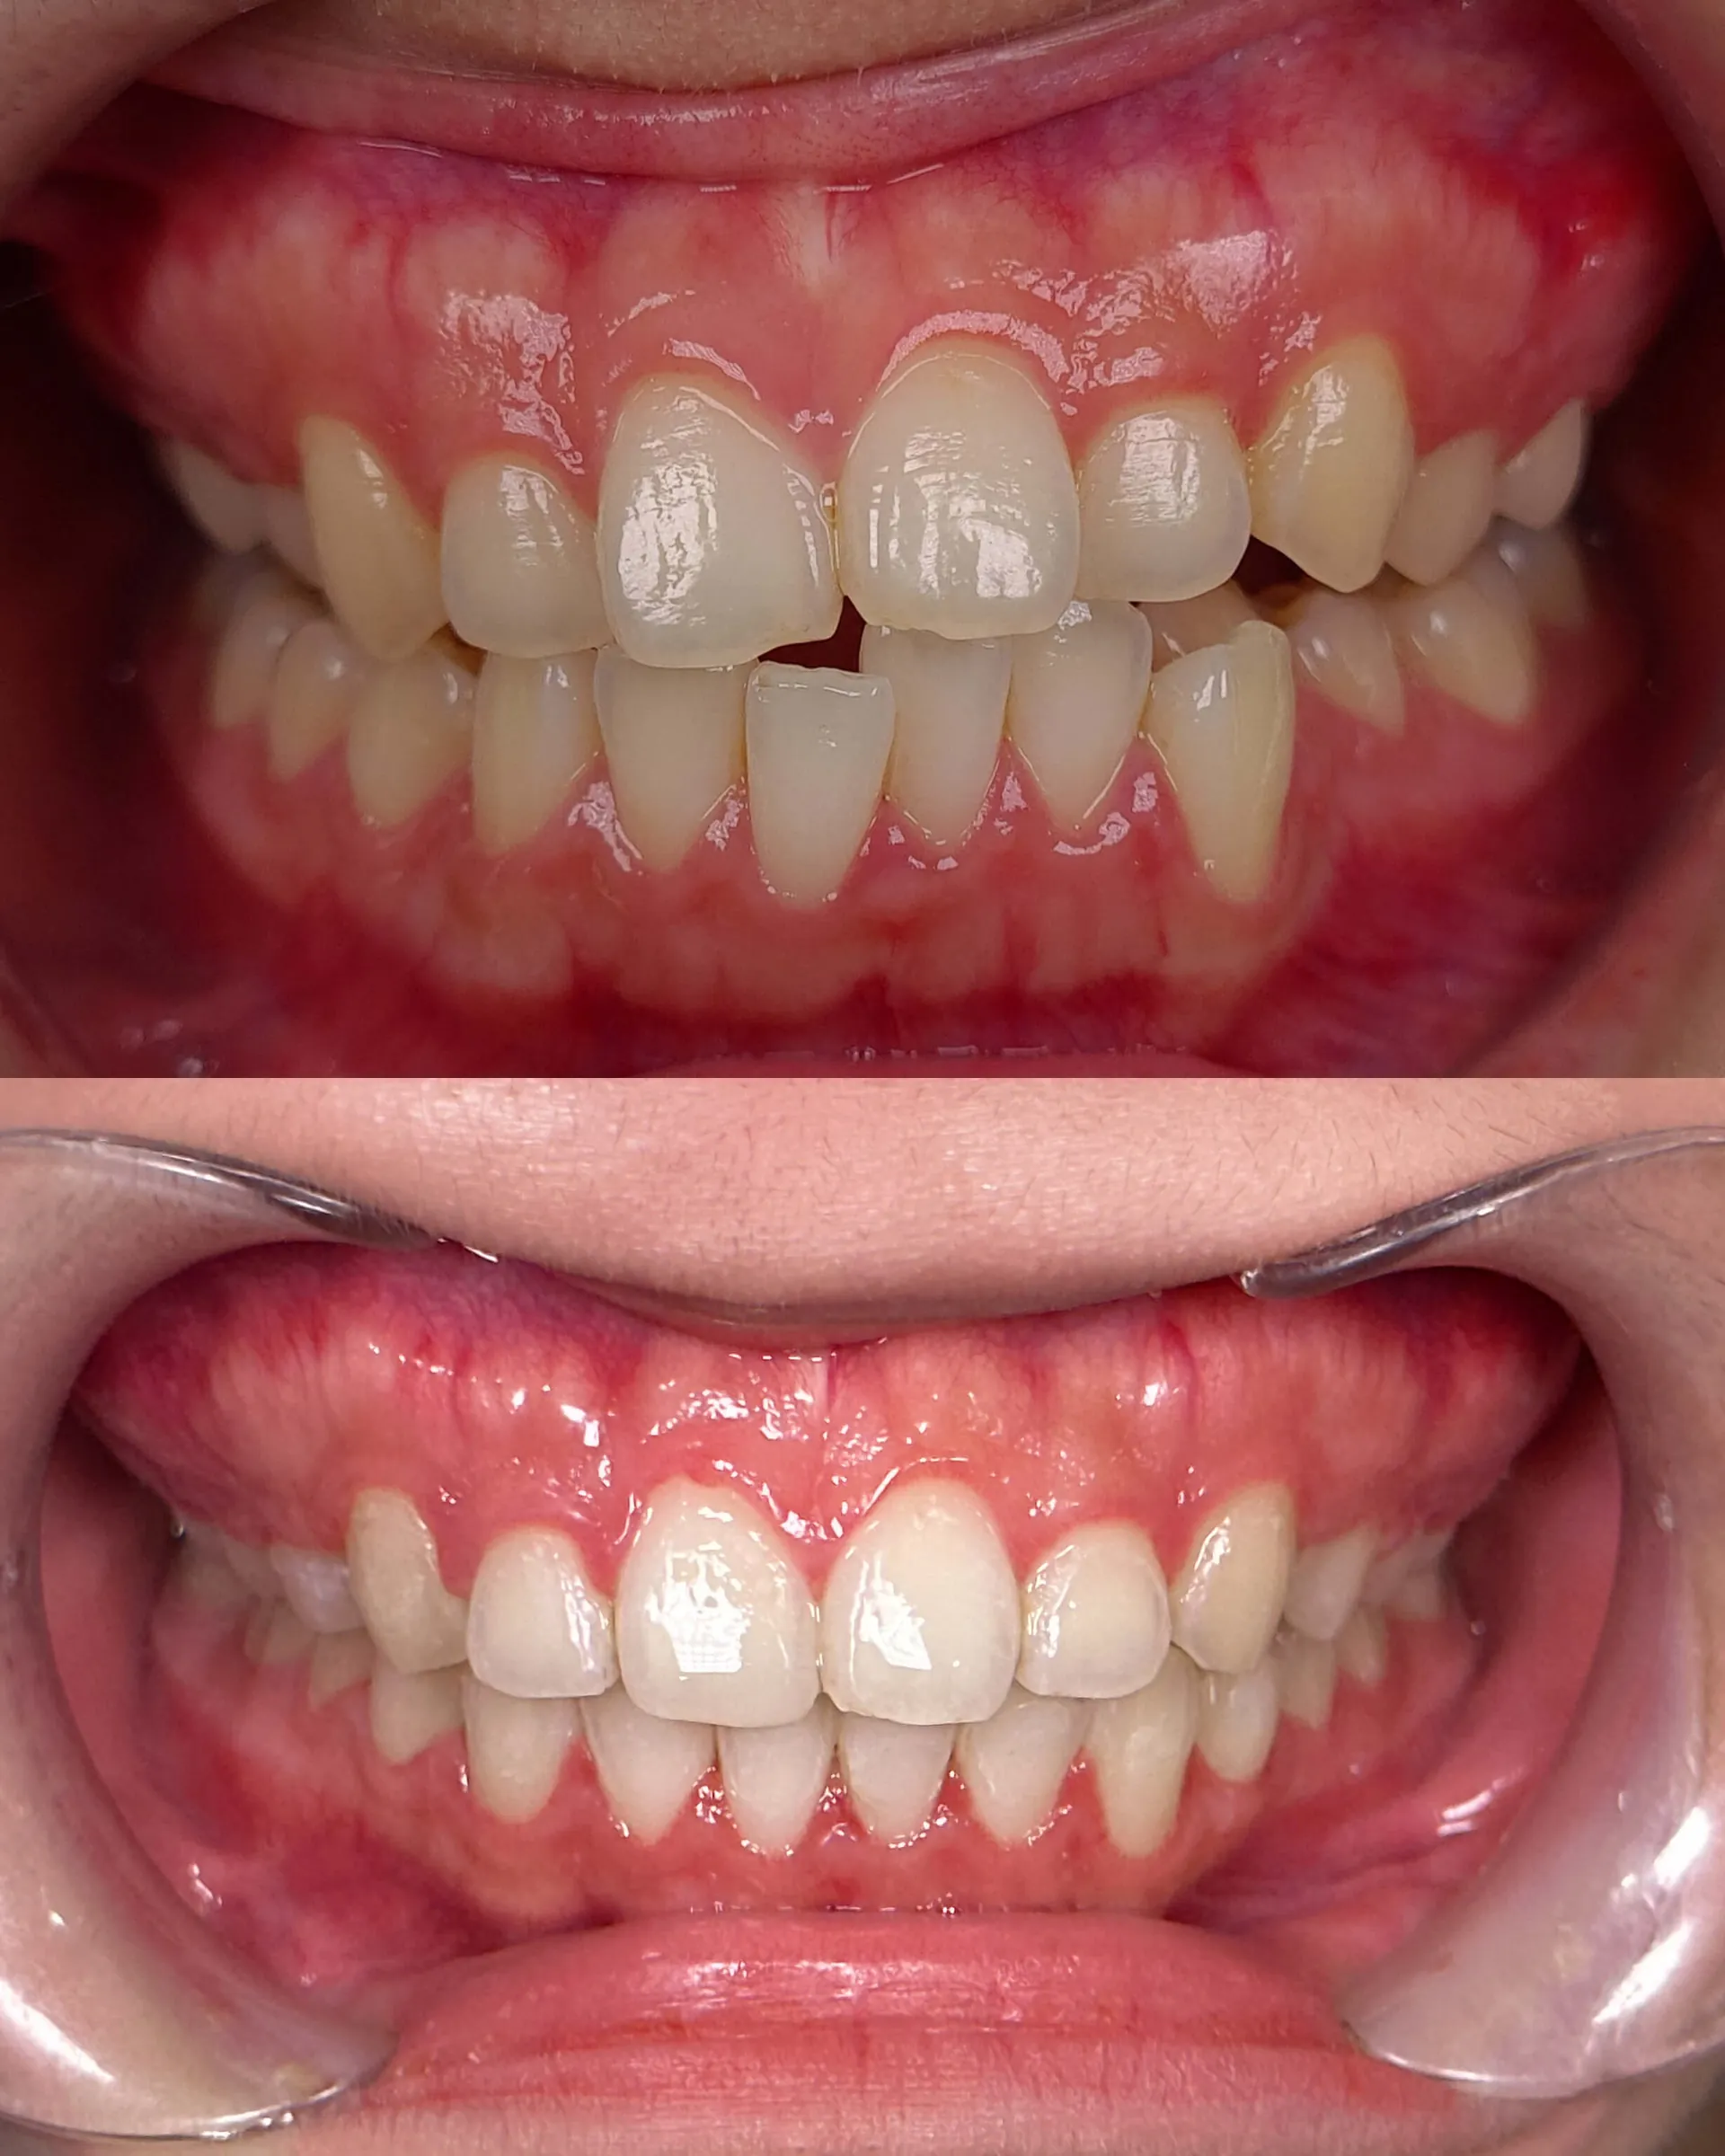

Invisalign®

As an award-winning Platinum Elite Invisalign provider, having completed over thousands of Invisalign® treatments, your smile is personally designed by our team of dentists for an aesthetically beautiful and functional end result using clear aligner technology to straighten your teeth.

Self Ligating Braces

Choose our self-ligating braces for a more comfortable orthodontic experience. Our innovative braces minimize discomfort and reduce treatment time. Enjoy fewer office visits and easier oral hygiene. Benefit from advanced technology and personalized care for effective, hassle-free orthodontic treatment. Unlock a confident smile with our self-ligating braces.